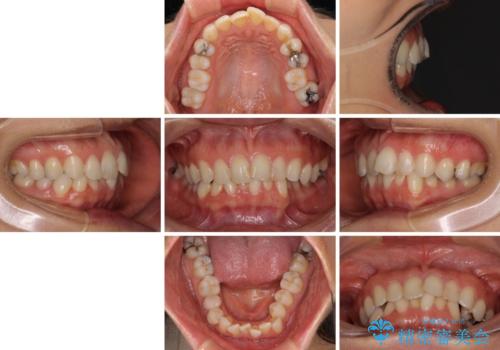

- 前歯のデコボコを気にして来院された患者様です。

IPR(歯と歯の間を削る)によってデコボコが解消するように設計し、インビザラインにより治療を行うこととしました。

下顎善の叢生をもう少し改善したかったのですが、患者様は十分に整ったとのことで治療を終えることになりました。